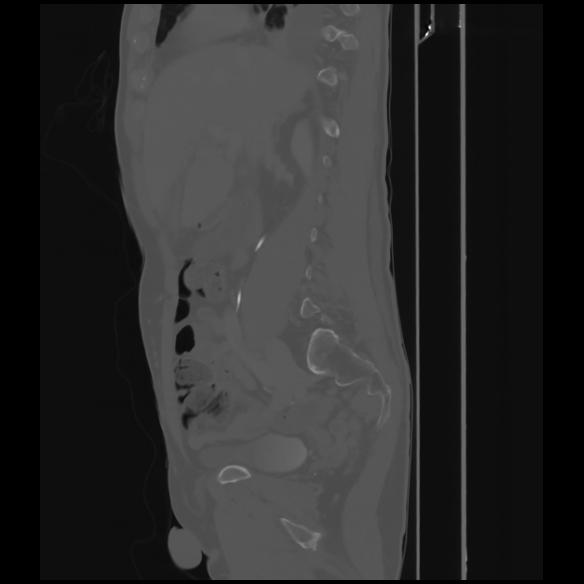

7 CUERPO,CE,Sagittal,3.000,CUERPO,Sagittal,